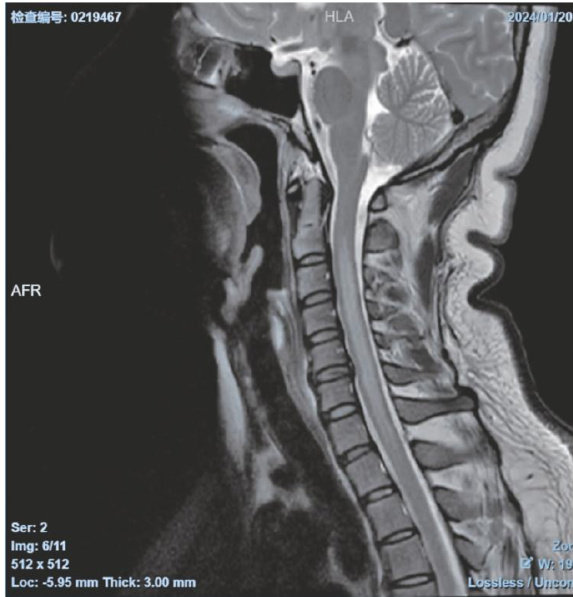

ABSTRACT:Listeria brainstem encephalitiswith myelitisisextremelyrare inclinical practice.Since the clinical manifestations are non-specific,MRI is helpful for diagnosis.Positive cerebrospinal fluid culture is considered thegold standard for diagnosis.Thisarticlereportsacaseof an immunocompetent individual with listeria brainstem encephalitis with myelitis,aiming to enhance the awareness of this condition.

单核细胞增生李斯特菌(Listeriamonocytogenes,LM)脑干脑炎合并脊髓炎在临床上较为罕见,该病呈双相病程,前驱症状呈非特异性,后出现一系列脑区受累症状,脑脊液培养阳性为诊断的金标准。(剩余9179字)